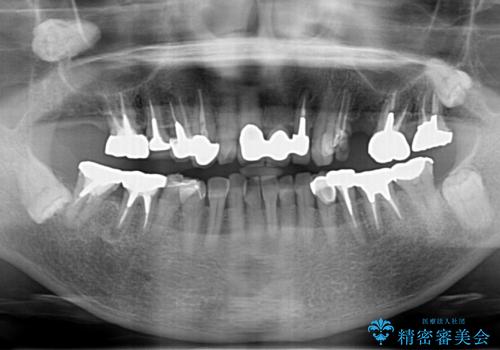

- 見た目の悪い銀歯や虫歯、歯の欠損、全体的な治療を希望されて来院されました。

インプラント治療や根管治療・セラミック治療を総合的に考えた精度の高い治療を計画し、しっかり噛めるようになるのはもちろん長期的な予後や審美性の向上を考えた全顎的な治療を実践していきます。

期間は約2年ほどかかりましたが、審美的な仕上がりとともに清掃のしやすさも非常に満足いただくことができました。